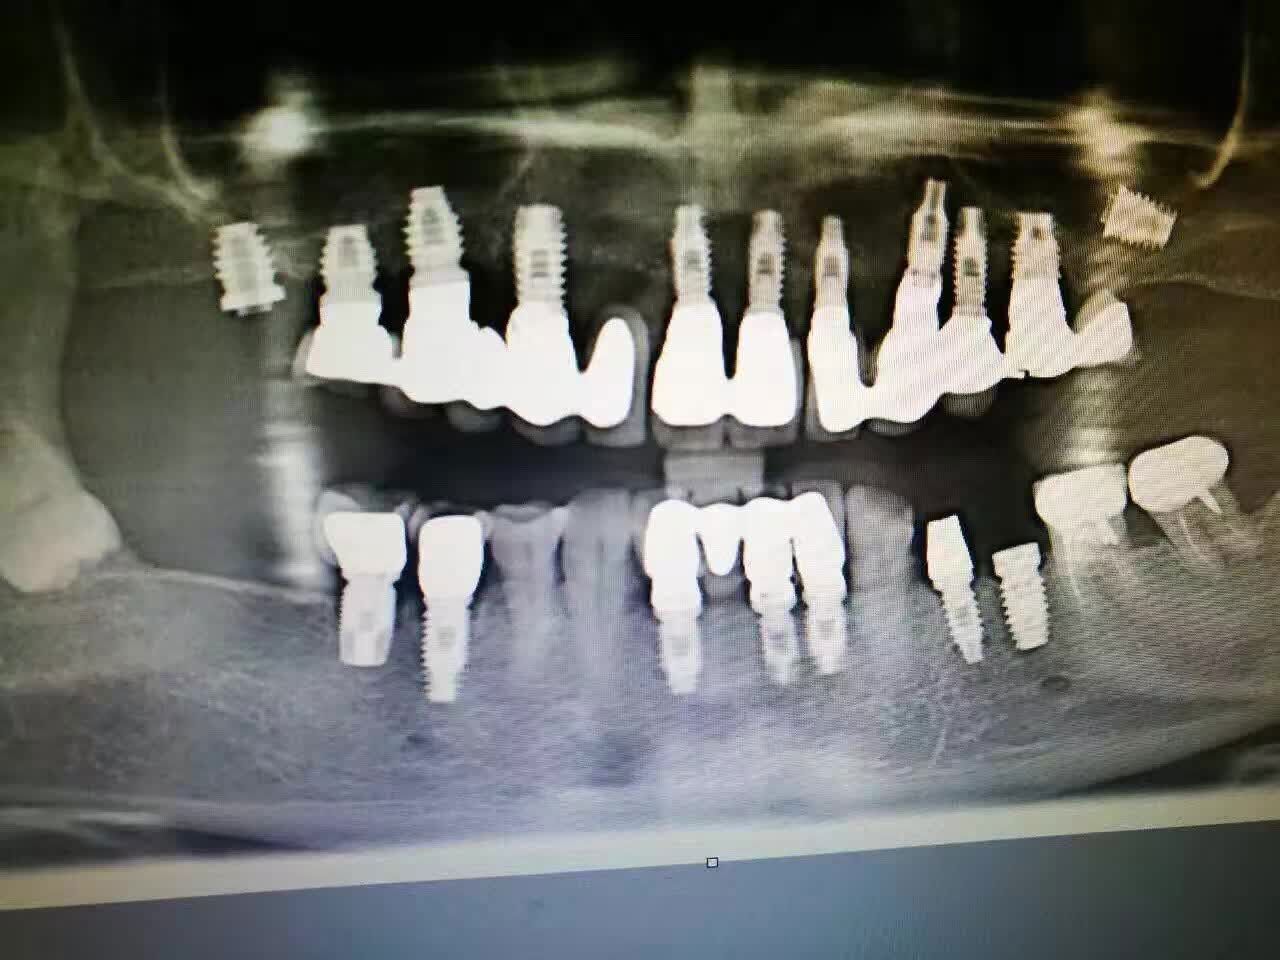

我院成功实施种植牙口腔全景图

成都春天牙科由华西种植医生谭教授亲自为顾客制定种植方案,并亲自种植。由于谭教授经验丰富、技术过关,且医德服人,得到了很多顾客的认可。预约谭教授亲自种植牙,可点击此处免费预约。